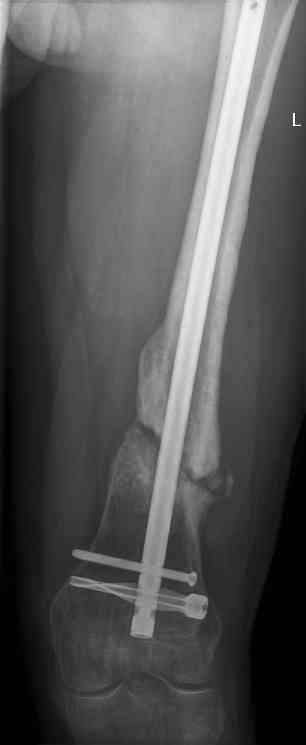

feb 07: retrograde nail + bone graft + BMP

may 07: dynamisation nail

sept 07: locking screw removal (max. dynamisation reached)

nov 07: persistant non-union distal femur; other fractures healed uneventfully.

All with gradual/partial weightbearing etc. Currently 50-100% weight bearing, no pain.